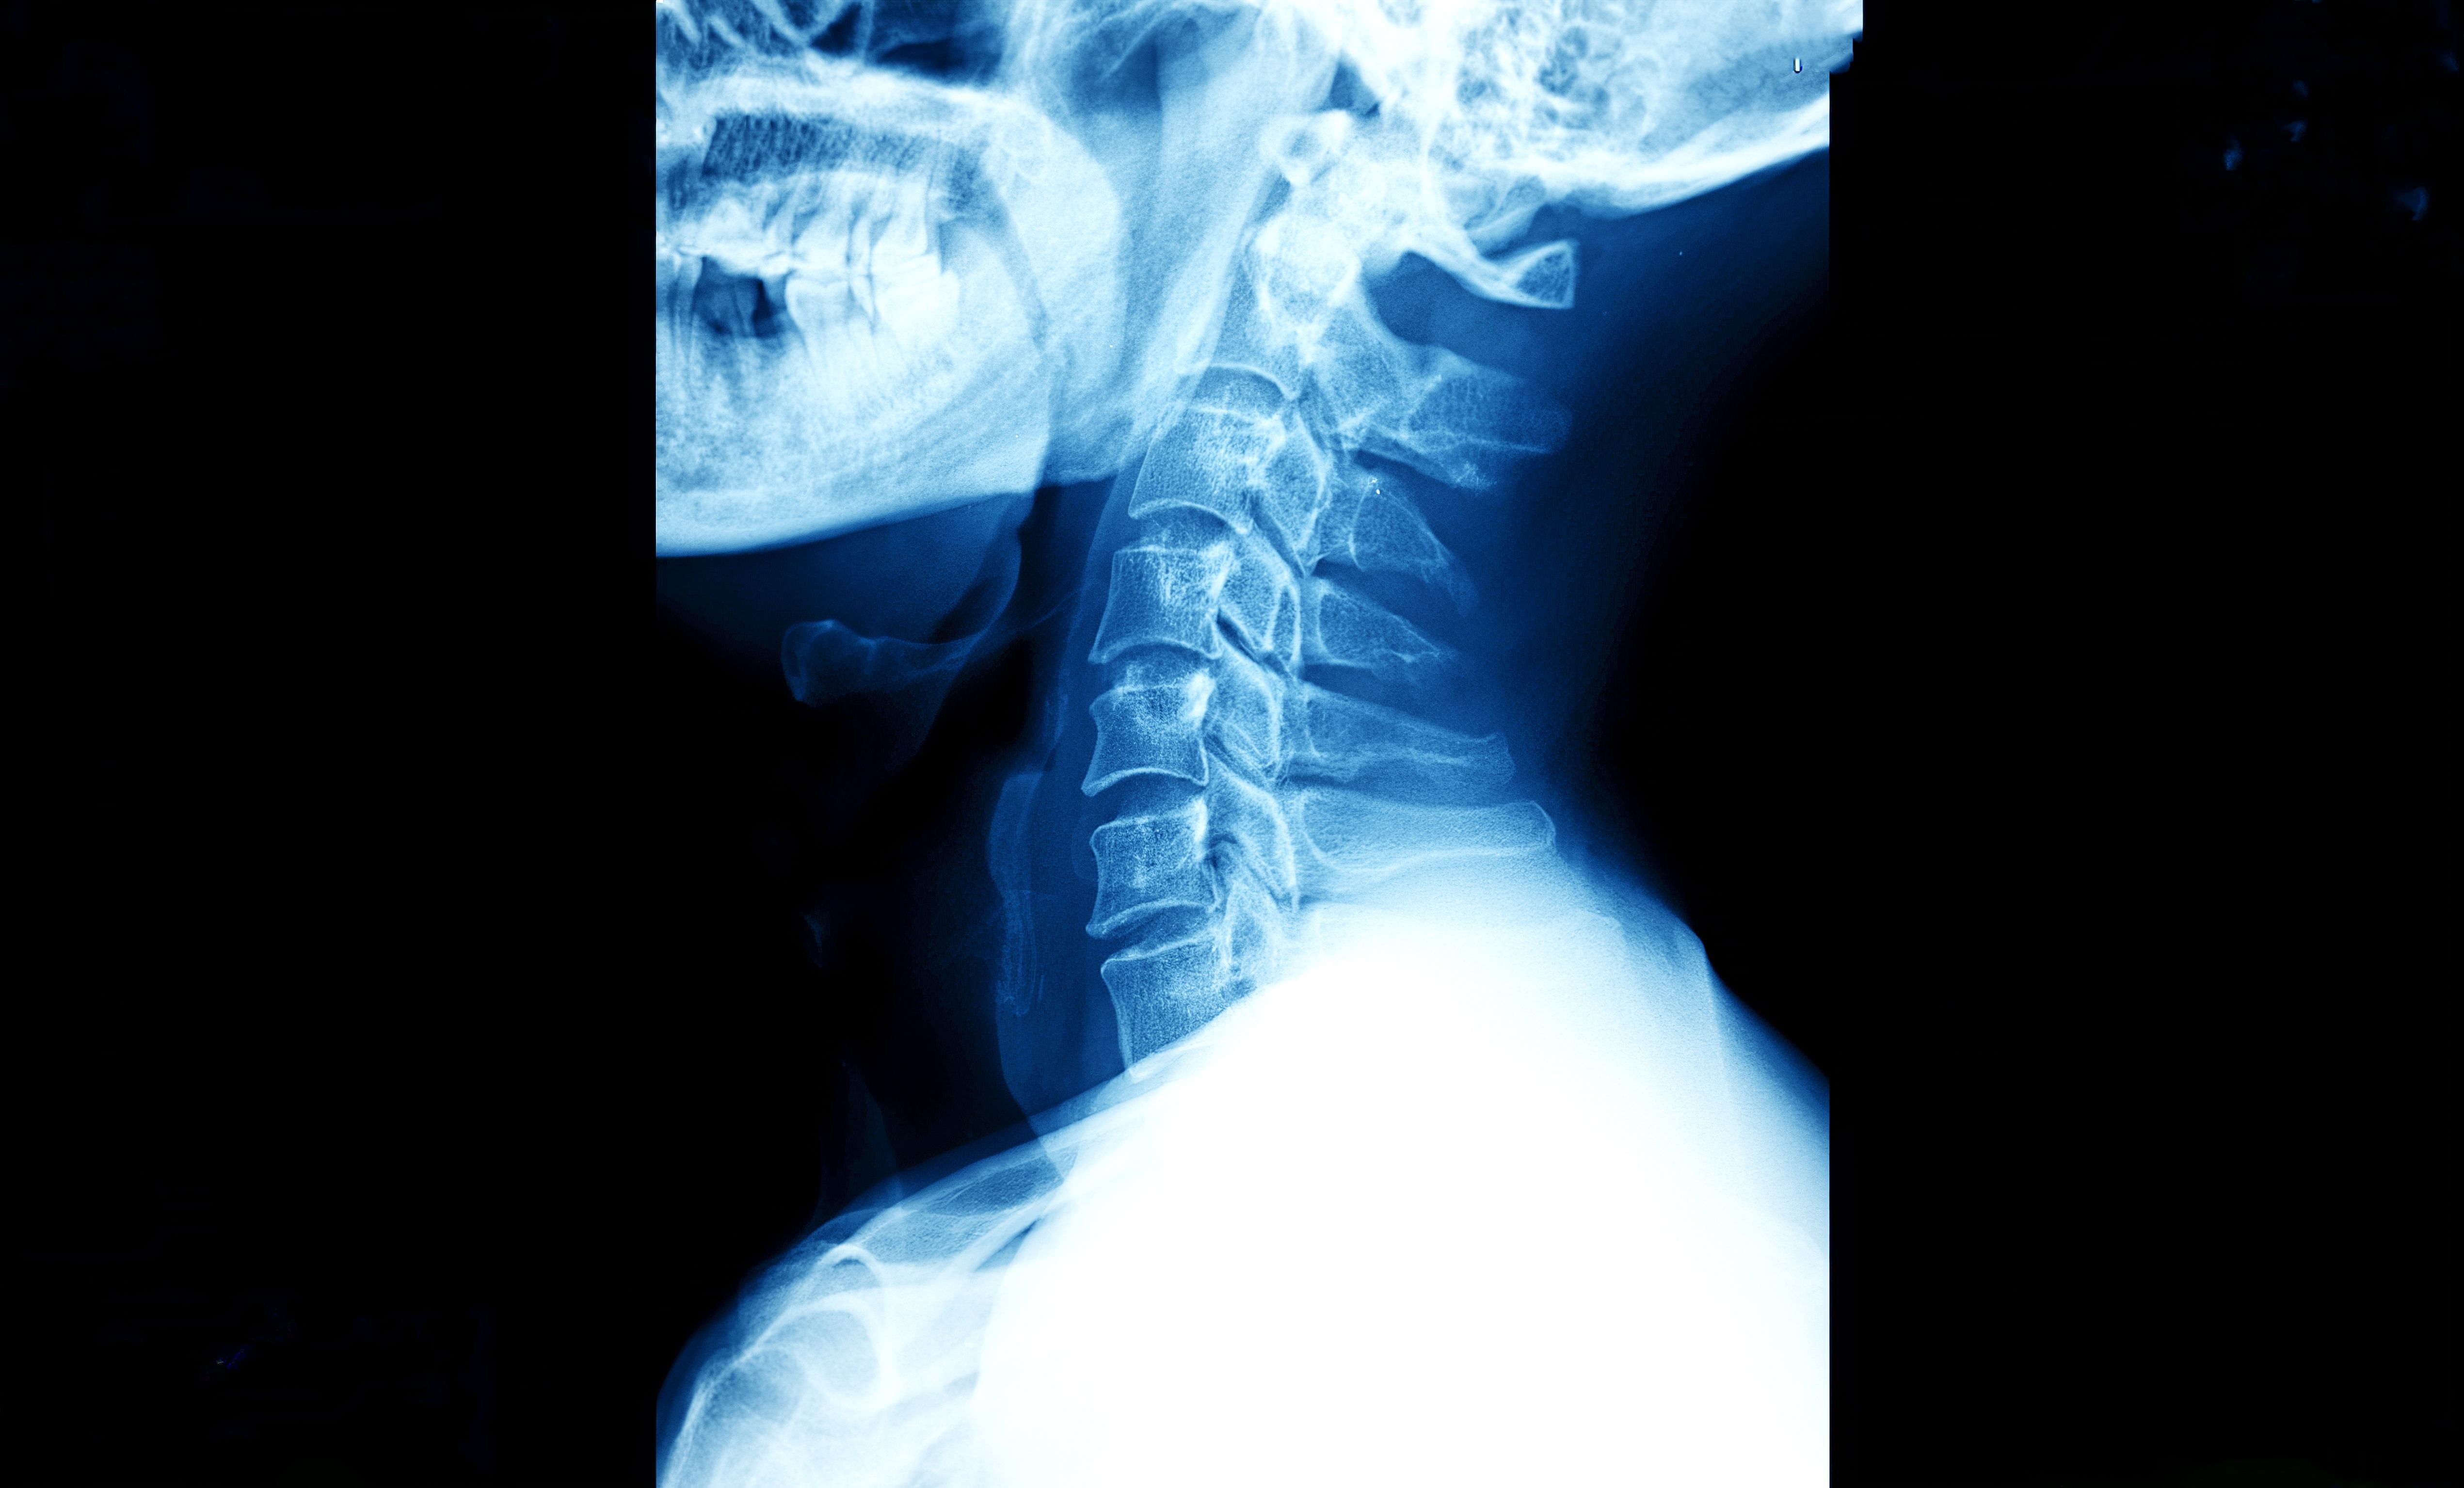

The spine consists of three main regions: The cervical spine (neck) with seven vertebrae, the thoracic spine (mid-back) with twelve vertebrae, and the lumbar spine (lower back) with five vertebrae.1 Multilevel degenerative disc disease can affect any combination of these regions, though the cervical and lumbar areas are most involved due to their greater mobility and weight-bearing demands.